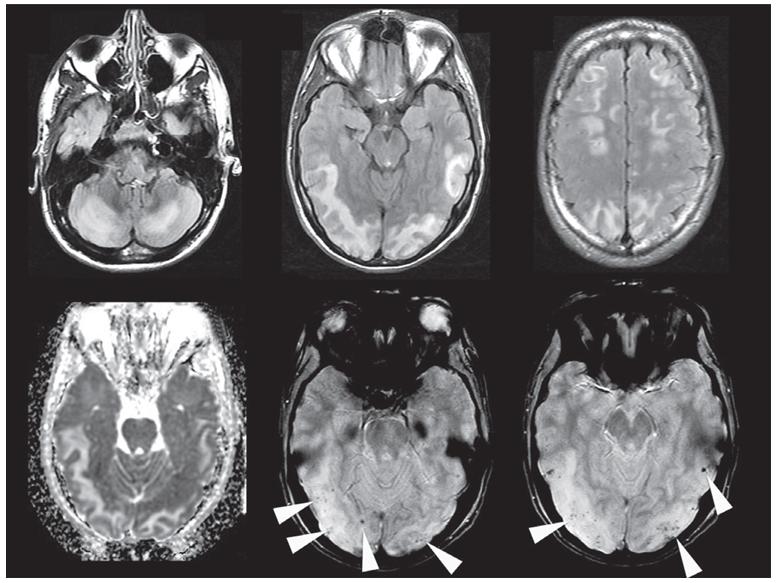

IE的MRI表现包括脑梗死(通常多发,无症状性,累及皮层及分水岭区)、细菌性动脉瘤(通常双侧多发,位于血管远端,呈梭形)、脑出血(ICH,与细菌性动脉瘤破裂或化脓坏死性局灶性动脉炎相关)、CMBs、脑脓肿及脑膜炎。

CMBs通常多发、皮层多见(皮层下白质、基底节、后颅窝少见)。CMBs可能提示化脓性血管炎或亚急性炎性微血管病变。小的细菌性动脉瘤和CMBs有时鉴别困难。

IE DWI示多发、小的、分水岭区梗死(a);T2*WI示皮层CMBs (b)。

PRES是一组由多种因素引起的以神经系统异常为主要表现的临床综合征。影像学特征为主要发生在脑后部的可逆性皮层下血管源性水肿。病变多分布在双侧顶枕叶等后部脑白质区,也可以累及额颞叶皮层下白质,极少数情况下累及脑干及丘脑(中央变异型 PRES)。

严重PRES患者MRI可见弥散受限,呈现细胞毒性水肿。出血并发症包括ICH、CSS和CMBs。其中CMBs发生率为58%。在PRES患者中,CMBs出现的数量少(平均3个),其出现可能与其他影像异常发生的严重程度相关。

PRES FLAIR示小脑(a)、皮质及皮质下(b, c)WMH,ADC高信号(d),符合血管源性水肿。T2*WI示皮质及皮质下多发CMBs。